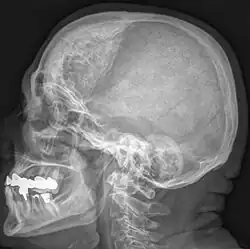

| Hyperostosis frontalis interna in a 74-year-old woman | |